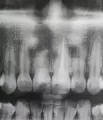

Поехала на консультацию к другому врачу, так как очень много сомнений. Другой врач сделал снимок, сказал, что киста большая и либо её надо лечить, либо удалять зуб. Сделал снимок, который показал, что пломбировочный материал вышел за пределы одного корня, а во втором остался осколок инструмента, и пробито дно зуба, но точно сказать не может, так как только при вскрытии зуба это будет видно. Каналы будут распломбированы. Но, если дно пробито - зуб только на удаление, не имеет смысла лечить каналы и кисту. А если нет, то медикаментозно, лекарствами, будут избавляться от кисты.

• На снимке определяется разрежение ткани в области пятого и дистального корня шестого зубов. Следует наблюдать в динамике, на фоне лечения возможно улучшение. В таком случае рекомендуется проводить контроль через 3,6,12 месяцев.

• По рентгеновскому снимку можно сказать, что в области бифуркации корней зуба есть очаг воспаления больших размеров, что является прямым показанием к удалению этого зуба. Перелечивание корневых каналов не даст положительного результата. После удаления, необходимо заместить отсутствующий дефект или мостовидным протезом или имплантатом.